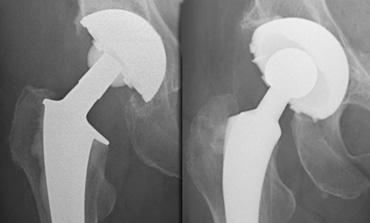

Total Hip Arthroplasty systems

LEFT: Assembled cementless Mallory Head prosthesis.RIGHT: Femoral stem with proximal porous coating for bone ingrowth, separate metal femoral head, polyethylene acetabular liner with a porous coated metal backing.

Hệ thống Thay khớp háng toàn phần (THA) hiện đại có cấu trúc mô-đun. Điều này có nghĩa là thân khớp đùi, chỏm khớp, vỏ ổ cối và lớp lót là các bộ phận riêng biệt.

Tính mô-đun này cho phép linh hoạt hơn trong việc tùy chỉnh kích thước và độ vừa khít của bộ phận giả.

Phần ổ cối thường là lớp lót polyethylene có hoặc không có đế kim loại.

Cố định bằng xi măng, đinh ghim, vít hoặc không xi măng với lớp phủ xốp để xương phát triển vào trong.

Phần đùi bao gồm thân khớp kim loại (hợp kim crom coban hoặc titan) và chỏm xương đùi bằng kim loại hoặc gốm sứ.

Cố định thân khớp cũng có thể bằng xi măng hoặc không xi măng với lớp phủ xốp để xương phát triển vào trong.

Hầu hết các THA không xi măng hiện đại có thân xương đùi chỉ được phủ lớp coating ở phần gần, vì điều này mang lại kết quả lâu dài tốt hơn so với phủ toàn bộ (ít bị lỏng hơn).

Một số THA không xi măng có thân xương đùi được phủ thêm lớp hydroxyapatite giúp cải thiện khả năng tích hợp xương. Lớp phủ này không hiển thị trên phim X-quang.